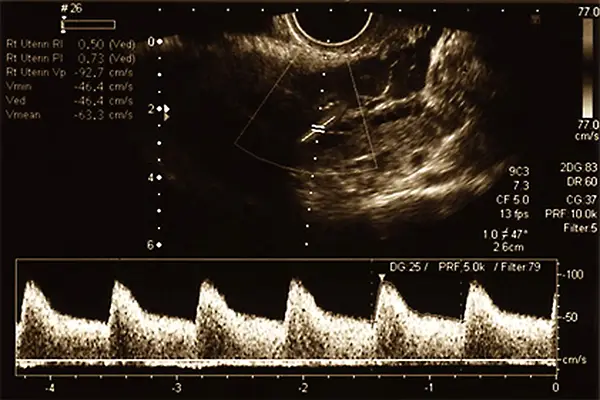

Die Duplexsonografie kombiniert herkömmliche Ultraschallbilder mit der Dopplersonografie und ermöglicht es dem Arzt, sowohl den Blutstrom als auch die Struktur der Gefäßwände gleichzeitig zu beurteilen. Dieses Verfahren bietet eine detailliertere Einsicht und ist besonders wertvoll für eine umfassende pränatale Diagnostik.